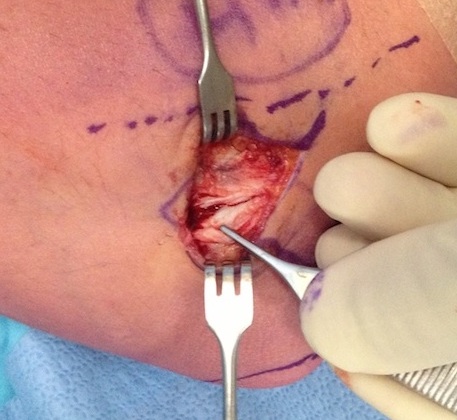

Open tennis elbow release

Technique

Incision centered on common extensor origin

- slightly anterior to radiocapitellar joint

- elevate ECRL (ECRL muscular at this point)

- ECRB is deep and posterior to ECRL

- detach ECRB from lateral epicondyle

- debride degenerative tissue and decorticate underlying common extensor origin

- +/- reattach ECRB with suture anchors

Post tennis elbow repair with anchor